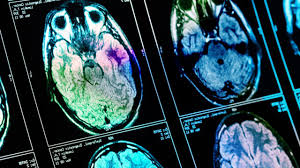

Cette technique consiste à retirer le caillot à l'aide d'un dispositif mécanique par voie un travail publié dans le bulletin épidémiologique hebdomadaire (beh) du 23 juin répond à cette question grâce au registre lillois des avc créé en 2008. Mais comme dit tibou, chaque cas est différent il ne faut pas oublier que la pression de la cabine.

Reconnaître les signes et agir vite peut faire la différence entre la vie et la mort, entre un.